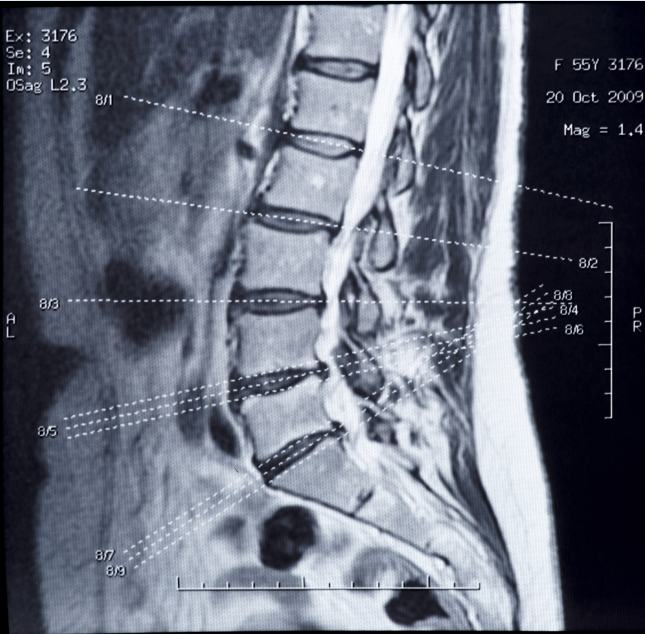

A 62-year-old man has moderate to severe leg pain after playing 36 holes of golf. The pain originates from the lumbar spine and radiates into his lower extremities. What is the best course of treatment?